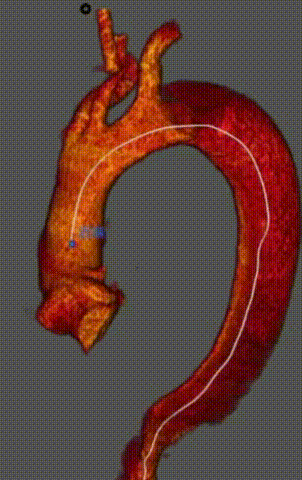

男性,35岁,TEVAR术后4月复查发现支架近端出现夹层

考虑为TEVAR术后逆撕,累及左颈总动脉

再干预方案:分支支架置入无名动脉,LCCA,LSA针刺原位开窗(方法:向近端延展)。

术前

术中

术后一周

术后4个月